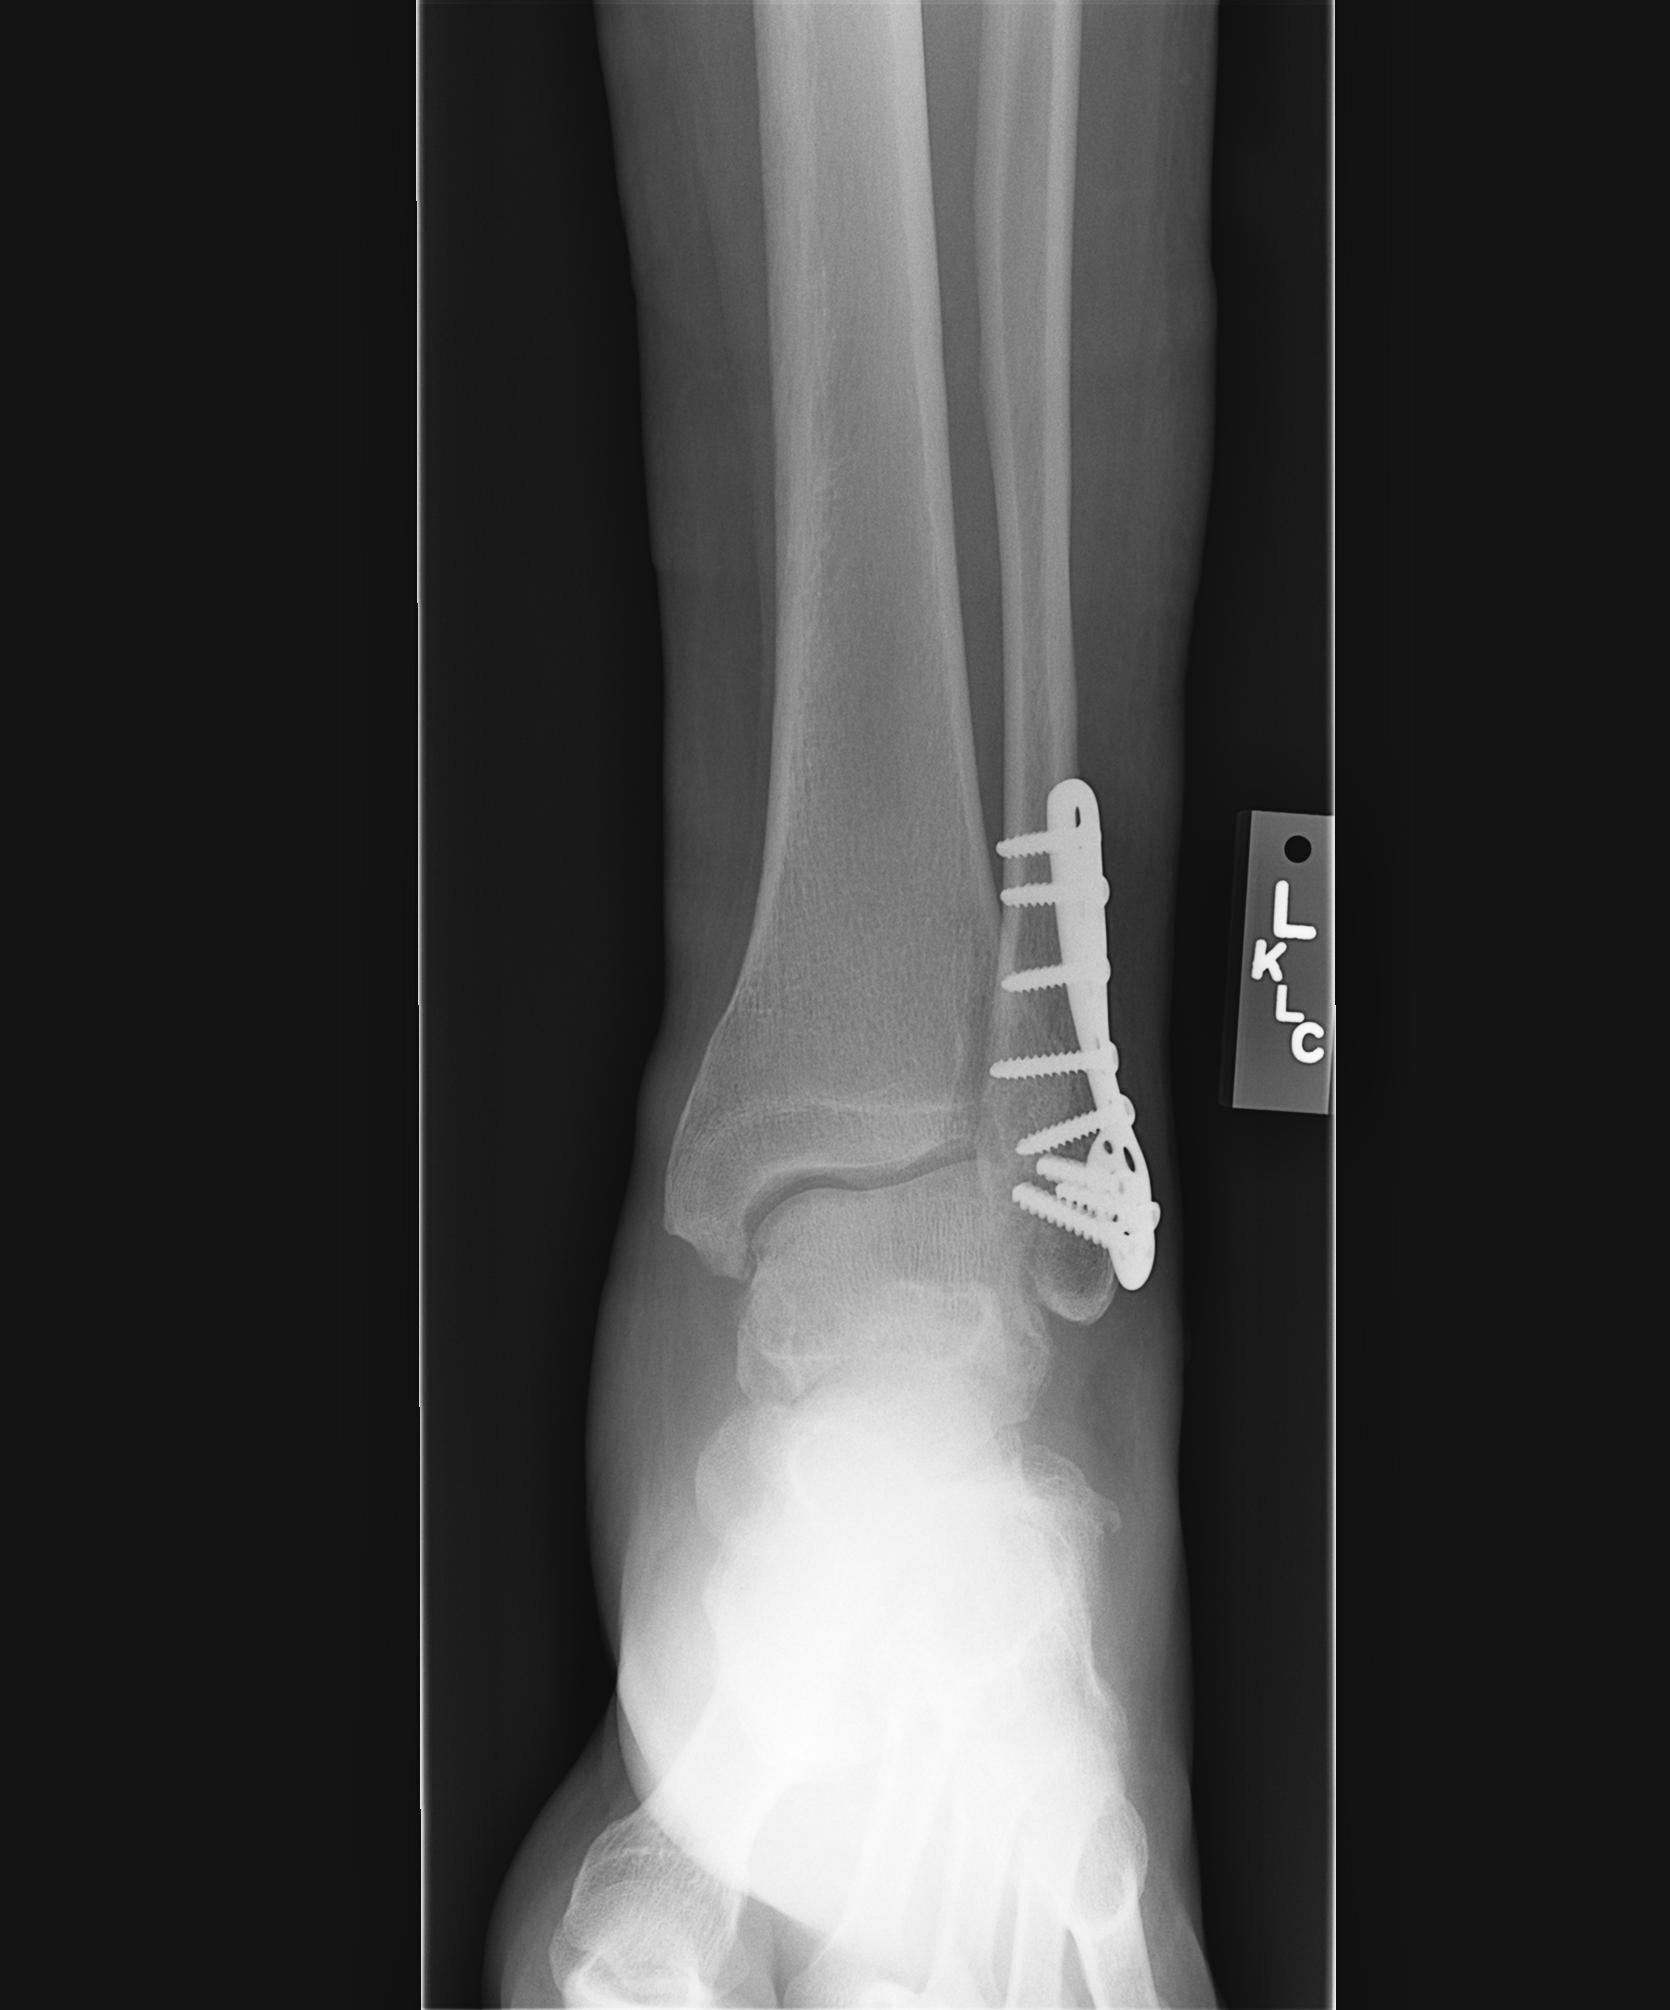

7-17-07

Dr. Visit 8-8-07 - The infection is healing and x-rays show most of the fracture has filled in. Look mid plate and to the left on x-ray #3 to see what is left of the fracture.